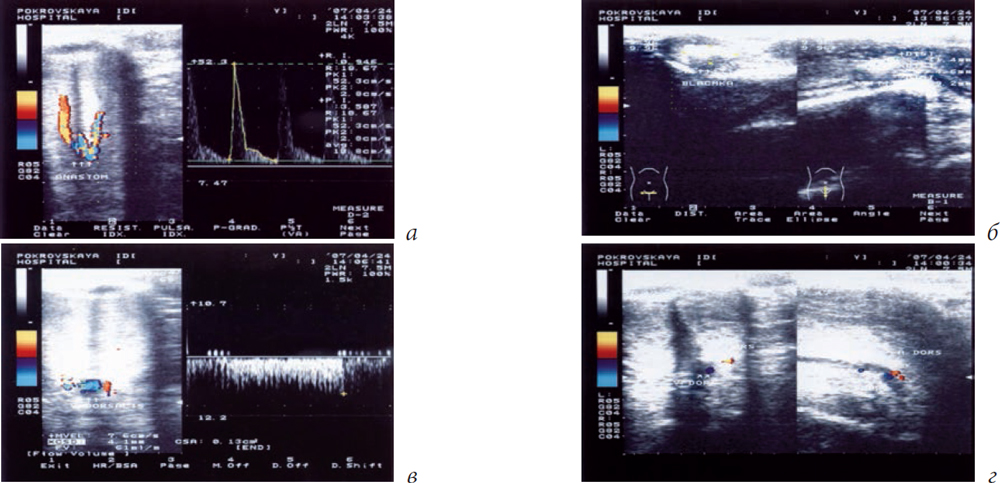

In performing ultrasound dopplerography on the penis, vascular changes were detected in 16 of the 27 patients examined, and 8 patients (50%) had manifestative venogenic compensated and subcompensated erectile dysfunction (Figures 2 and 3). The remaining 11 patients had no signs of vascular changes (Table 1).

Fig. 2. Ultrasound dopplerography of the penis of Patient D (36 years old with Peyronie’s disease and venogenic erectile dysfunction): a) in the distal part of the penis, the plaques are from 1–2 to 8.5 mm; b) the dorsal vein did not collapse, and blood flow along it was 30 ml/min. Valsalva test was positive

Fig. 3. Ultrasound dopplerography of the penis of Patient T (55 years old with Peyronie’s disease and venogenic erectile dysfunction). The patient has Dupuytren’s contracture: a) abnormality of the structure of the cavernous arteries, i.e., anastomosis of the cavernous arteries in the crus of the penis; b) plaques in the cavernous bodies (plaque of 11.4 mm × 4.6 mm × 9.2 mm is marked), which deformed the penis; c) and d) noncollapse concurrence of the dorsal vein as a sign of venous erectile dysfunction